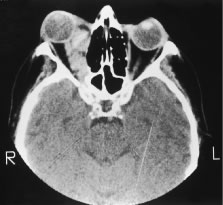

The incidence of cancer metastatic to the orbit ranges from 2% to 9% of orbital neoplasms.9,10,12,33 Orbital metastases usually occur more commonly in women between the ages of 40 to 60 years. The presenting signs in patients with metastatic cancer to the orbit include proptosis or rarely enophthalmos; a painful, palpable mass; and ophthalmoplegia. Less common signs include vision loss, choroidal folds, or an afferent pupillary defect14 (Fig. 6). The reported primary malignancies includes breast cancer, lung cancer, gastrointestinal cancer, genitourinary tract cancers, thyroid cancer, adrenal cell cancer, and cutaneous malignant melanoma.9,10,12,33 We have reported a case of uveal malignant melanoma metastatic to the contralateral eye and orbit.16 Neuroblastoma,12,33 Ewing's sarcoma,19 and Wilms tumor12,33 have been known to metastasize to the orbit in children.

Fig. 6. Computerized axial tomography scan of head, axial section, in a patient with metastatic breast cancer to the right orbit.